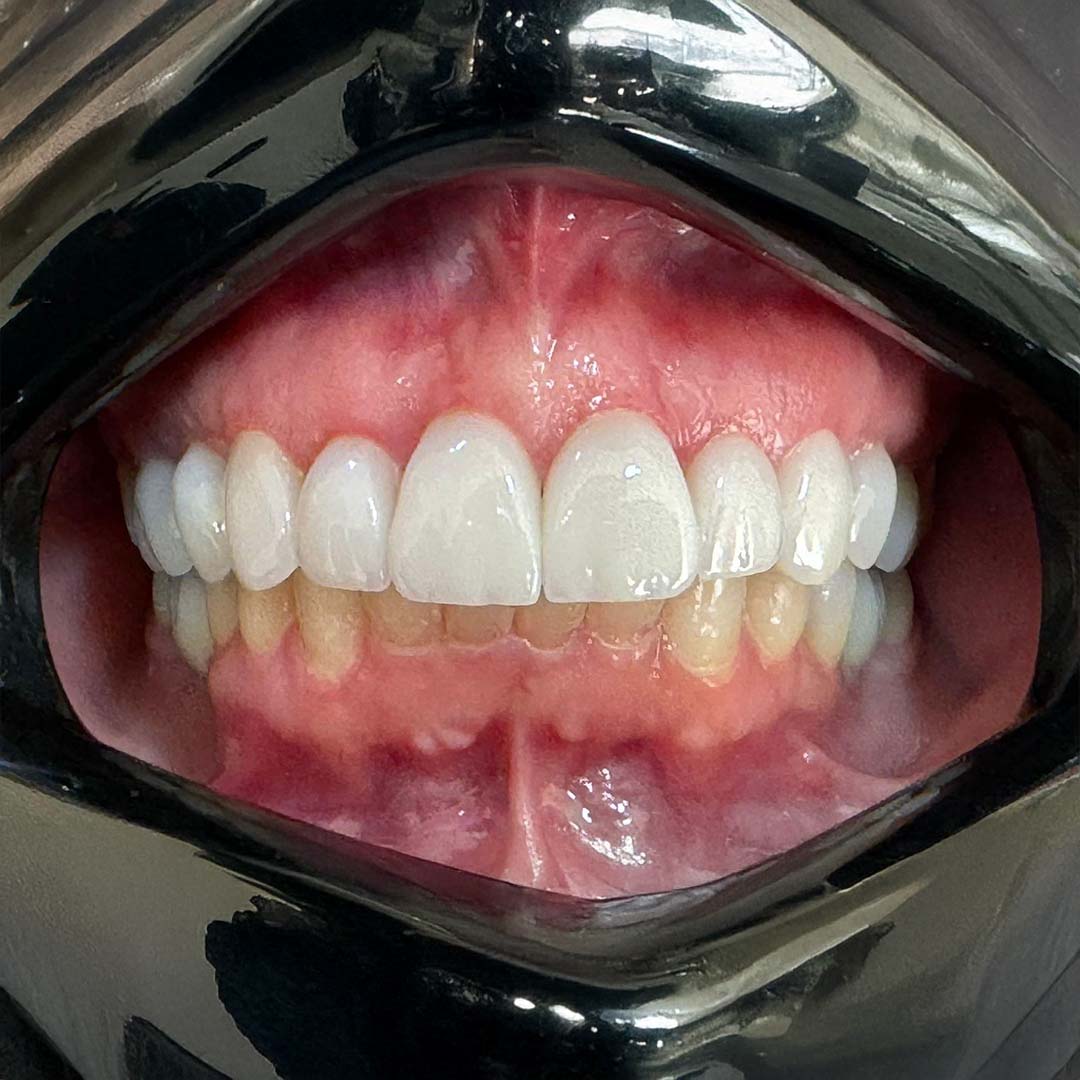

Veja os resultados que falam por si

Antes e depois de pacientes que confiaram na Molino para transformar seus sorrisos e recuperar a autoestima.